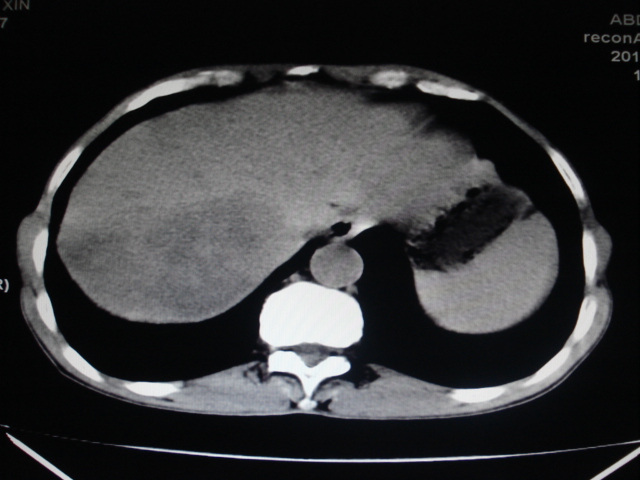

男性,62岁。肝右叶占位,平扫及增强如下,延迟期为15分钟扫描。